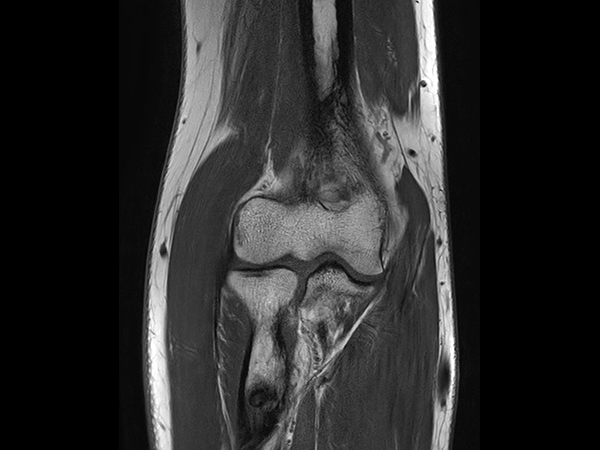

PDw TSE FatSat Compressed SENSE

T1w TSE Compressed SENSE

T2w TSE MultiVane XD FatSat